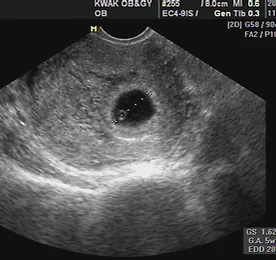

드디어 확인!! 자유 Jr. 자유 Jr.를 오늘 드디어 확인했다. :) 그 동안 아기를 기다려온 기간이 꽤 길었는데, 지난 주부터 색시의 몸 상태가 예전과 다르더니, 임신 테스트에서도 두 줄이 나왔고, 오늘 가 본 병원 초음파에서도 아기집을 확인했다. :) 오래 기다려온 만큼 그 기쁨도 크다. 물론, 한 여자의 남편이라는 것보다 더 크게 다가오는 한 아이의 아빠라는 이름, 이 이름이 부끄럽지 않도록 열심히 살아야겠다는 다짐도 해 본다. 앞으로 임신과 출산, 그리고 육아에 대한 이야기는 Love 자유 쩜 오알지에 쓸 계획이다. 색시는 직접 손으로 임신일기를 쓰고, 나는 블로그를 통해 임신일기를 쓸거다. 더보기

임신의 확정징후, 첫 번째 초음파 사진 임신을 확인하는 징후에는 몇 가지 범주가 있는데, 그 중 가장 확실한 것, 그러니까 확정징후는... 1. 태아의 심박동 확인 2. 검사자에 의한 태동 확인 3. 배아 혹은 태아의 확인 으로 정리할 수 있다. 뭐, 이런 고리타분한 이야기를 하자는 것이 아니고, 임신 테스트 양성 확인을 하고 임신의 가정징후 몇 가지를 색시가 겪고 있었는데, 임신을 확신하기엔 좀 이르지 않을까 하는 생각에 우리끼리 쉬쉬하고 있었다가 오늘 색시 손 잡고 초음파로 확인해 보러 산부인과병원에 가 보았다. 초음파를 시작하자마자 보이는 저 것! 나는 직감했다. 우리 아기구나. :) 선생님의 설명도 듣고, 초음파 화면을 같이 보니 LMP 기준 약 5주 정도 되었다고 했다. 그렇다면!!! 우리가 지난 여름휴가로 제주도 다녀왔던 바로 그 .. 더보기